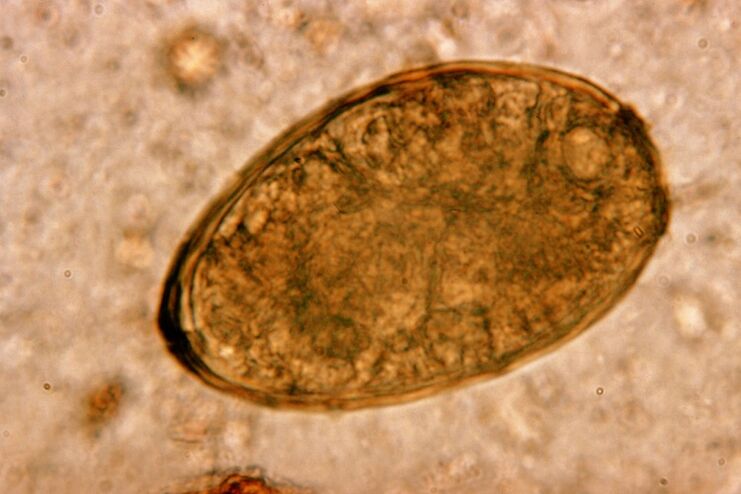

Kebetulan pulmonari helminth kecil, yang dimiliki oleh kelas trematoda, "mengkhususkan diri" dalam parasit khusus di dalam paru -paru. Ia menyebabkan masalah yang lebih serius dalam sistem pernafasan daripada cacing bulat, contohnya.

Di tapak penyetempatannya, infiltrat muncul dan pendarahan berkembang, akibatnya rongga kelihatan penuh dengan metabolit cacing, parasit mati dan tisu paru -paru. Kemudaratan dari kebetulan pulmonari semakin teruk oleh fakta bahawa ia adalah hati yang panjang dan boleh hidup di dalam badan tuan rumah sehingga 20 tahun.